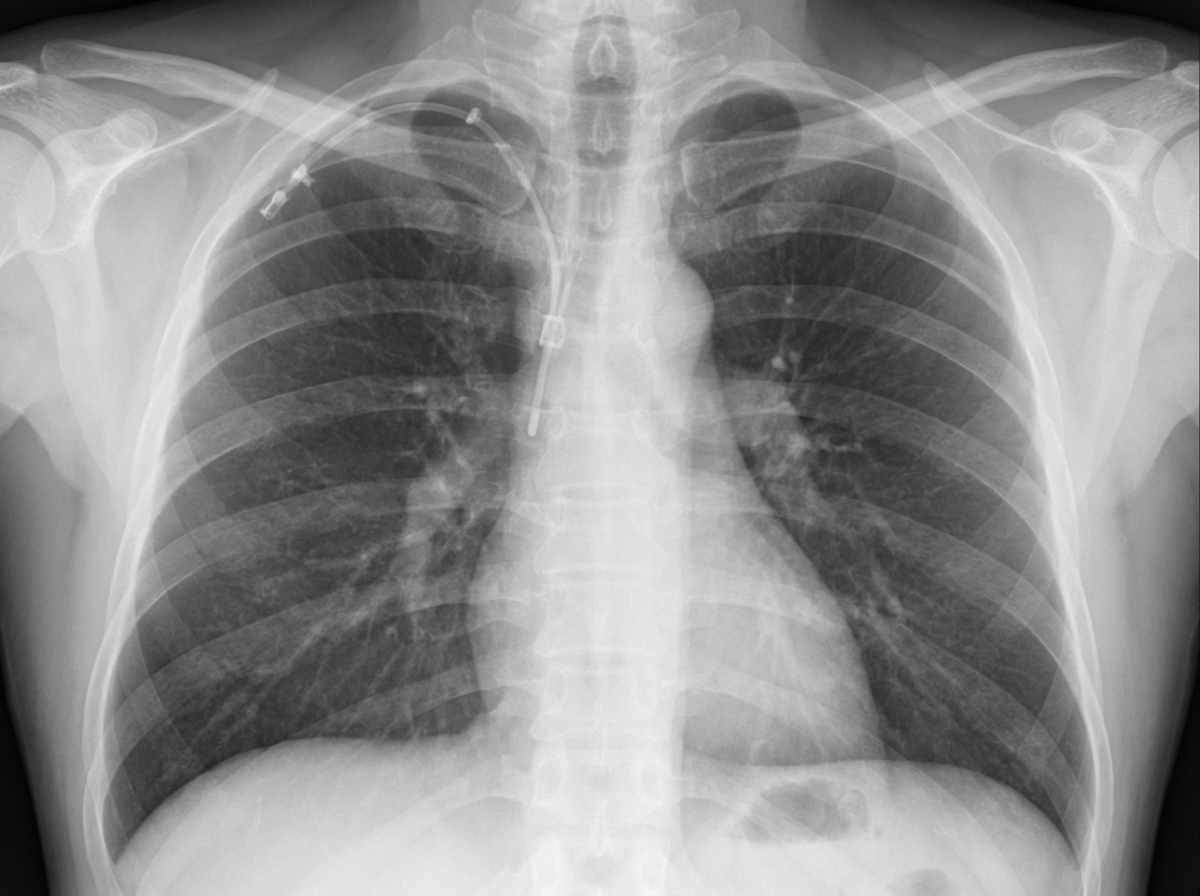

Explanation: ***Refeeding*** - The image shows a **central venous catheter (CVC)**, likely in the internal jugular vein. While CVCs are used for administering nutrition such as **total parenteral nutrition (TPN)**, refeeding syndrome is a metabolic complication that occurs when nutrition is reintroduced too quickly in severely malnourished patients. - **Refeeding syndrome is NOT a direct complication of the CVC insertion procedure itself**—it is a systemic metabolic complication related to the nutritional intervention (characterized by severe shifts in fluids and electrolytes, particularly hypophosphatemia, hypokalemia, and hypomagnesemia). - Therefore, refeeding is **not associated with the procedure** of CVC insertion. *Pneumothorax* - **Pneumothorax** is a well-recognized mechanical complication of central venous catheterization, particularly with subclavian and internal jugular vein approaches. - Occurs due to accidental puncture of the **pleura** during needle insertion, allowing air to enter the pleural space and causing lung collapse. - Incidence ranges from 1-6% depending on the site and operator experience. *Arrhythmia* - **Cardiac arrhythmias** are a known complication during CVC insertion when the guidewire or catheter tip inadvertently advances too far into the heart chambers (right atrium or ventricle). - Mechanical irritation of the myocardium can trigger **premature ventricular contractions (PVCs)** or other arrhythmias. - Usually transient and resolve upon withdrawing the catheter to proper position. *Aspiration* - While **aspiration** can occur in critically ill patients who require CVCs (due to altered consciousness, dysphagia, or ventilator-associated issues), it is **not a direct mechanical complication of the CVC insertion procedure itself**. - Aspiration relates to patient condition rather than the catheter placement technique, though both may coexist in the same clinical scenario.